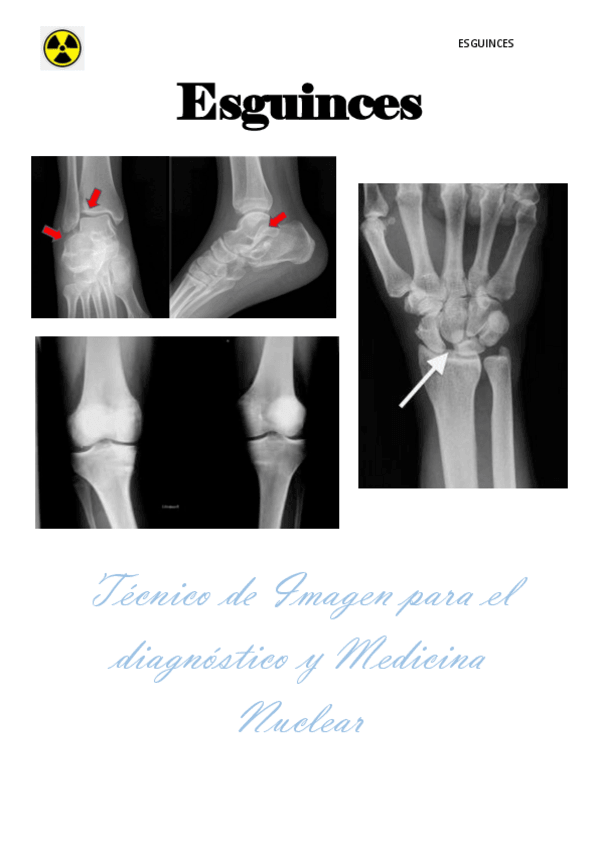

Proyecto final de grado de esguinces

13 páginas